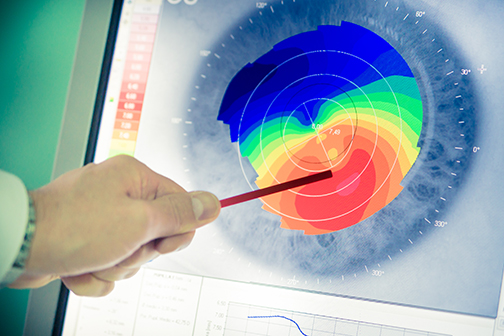

LSU Health New Orleans Researchers Discover a Key Failure in AMD that May Lead to Progression & Vision Loss

Research led by Nicolas Bazan, MD, PhD, Boyd Professor, Ernest C. and Yvette C. Villere Chair for the Study of Retinal Degeneration, and Director of the Neuroscience Center of Excellence at LSU Health New Orleans School of Medicine, suggests that age-related macular degeneration (AMD) decreases an essential fatty acid, preventing the formation of a class of protective molecules and reducing repair potential. The discovery may also open new therapeutic avenues for AMD. More

LSU Health New Orleans Develops New Human Cell Line to Study Blinding Eye Disorders

Under the direction of Boyd Professor Nicolas Bazan, MD, PhD, scientists at LSU Health New Orleans Neuroscience Center of Excellence have developed a new, experimental human cell line from retinal pigment epithelial cells. Called ABC, these cells so closely resemble and retain the properties of native retinal pigment epithelial (RPE) cells, the research team has shown that they are a reliable cell system to study retinal degenerative diseases. More